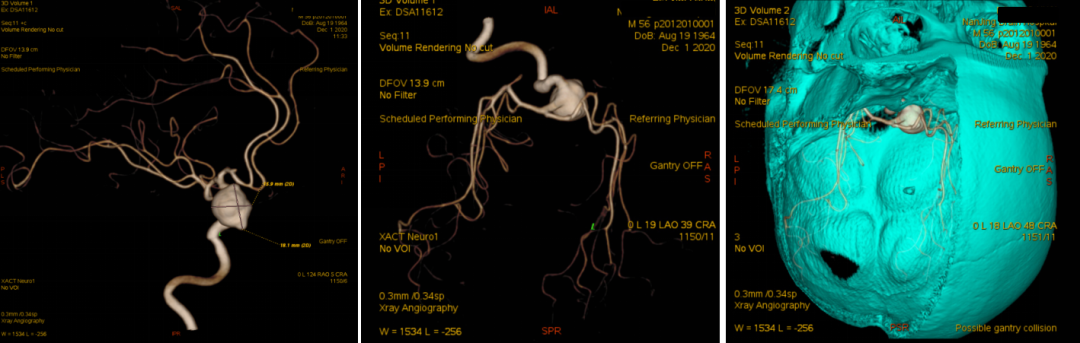

术后第1天CT

术后第1天CTA

患者术后病情稳定,神清,语明,双侧瞳孔等大等圆,直径约2.5mm,光反应灵敏,视力及视野正常,四肢肌力、肌张力正常。